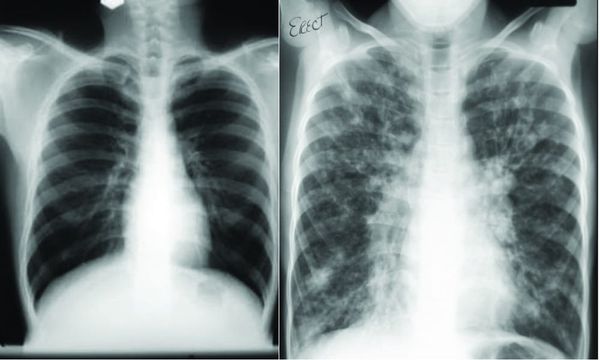

Tackling Cystic Fibrosis

Tackling Cystic Fibrosis through the ultimate endurance trust